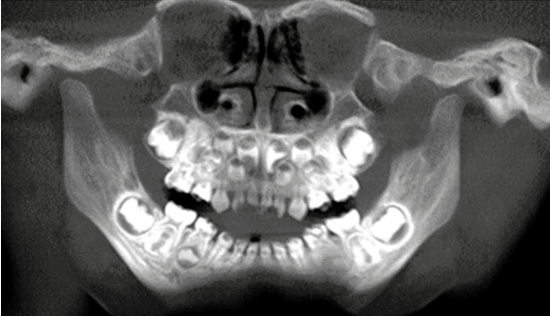

Antes de comenzar con el tratamiento se le realizó una tomografía axial computarizada en la que se observaron presentes y completos los órganos dentarios de ambas denticiones, apreciándose lesiones cavitadas y espesor reducido del esmalte (figura 3). Se comenzó la terapia de choque (uso de barnices alternados de CHX y flúor) para detener las lesiones cariosas incipientes y remineralizar las superficies dentales antes de su restauración. En la primera cita se comenzó aislando relativamente los dientes y se secaron con ayuda de gasas, se colocó el barniz de flúor (DuraShield®) sobre todas las superficies dentarias a manera de brochazo horizontal con la finalidad de impregnar bien este; se mantuvo el aislamiento relativo por al menos tres minutos y se dejó que el paciente se retirara sin enjuagarse y con indicaciones de no lavarse los dientes hasta el día siguiente y hacer un cambio de cepillo dental; se habló con los padres para moderar la ingesta de carbohidratos y alimentos con alto contenido de azúcar (figura 4).

Figura 3.Tomografía axial computarizada.